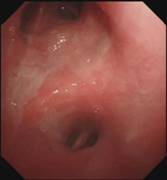

当最后一块异物被取出,患者的气管终于露出了原来的“庐山真面目”:

那堆长达18厘米的痰痂、血痂和痰栓不仅是这次急救成功的有力证明,也让人深感气道管理的重要性。

对于气管切开患者,定期监测气道状况并及时清理分泌物至关重要。同时,本次事件更凸显了支气管镜在处理紧急气道阻塞情况中的关键作用。呼吸介入团队面对挑战时迅速而精准的反应以及展现出的卓越专业技能,无疑是本次成功救治的关键因素。